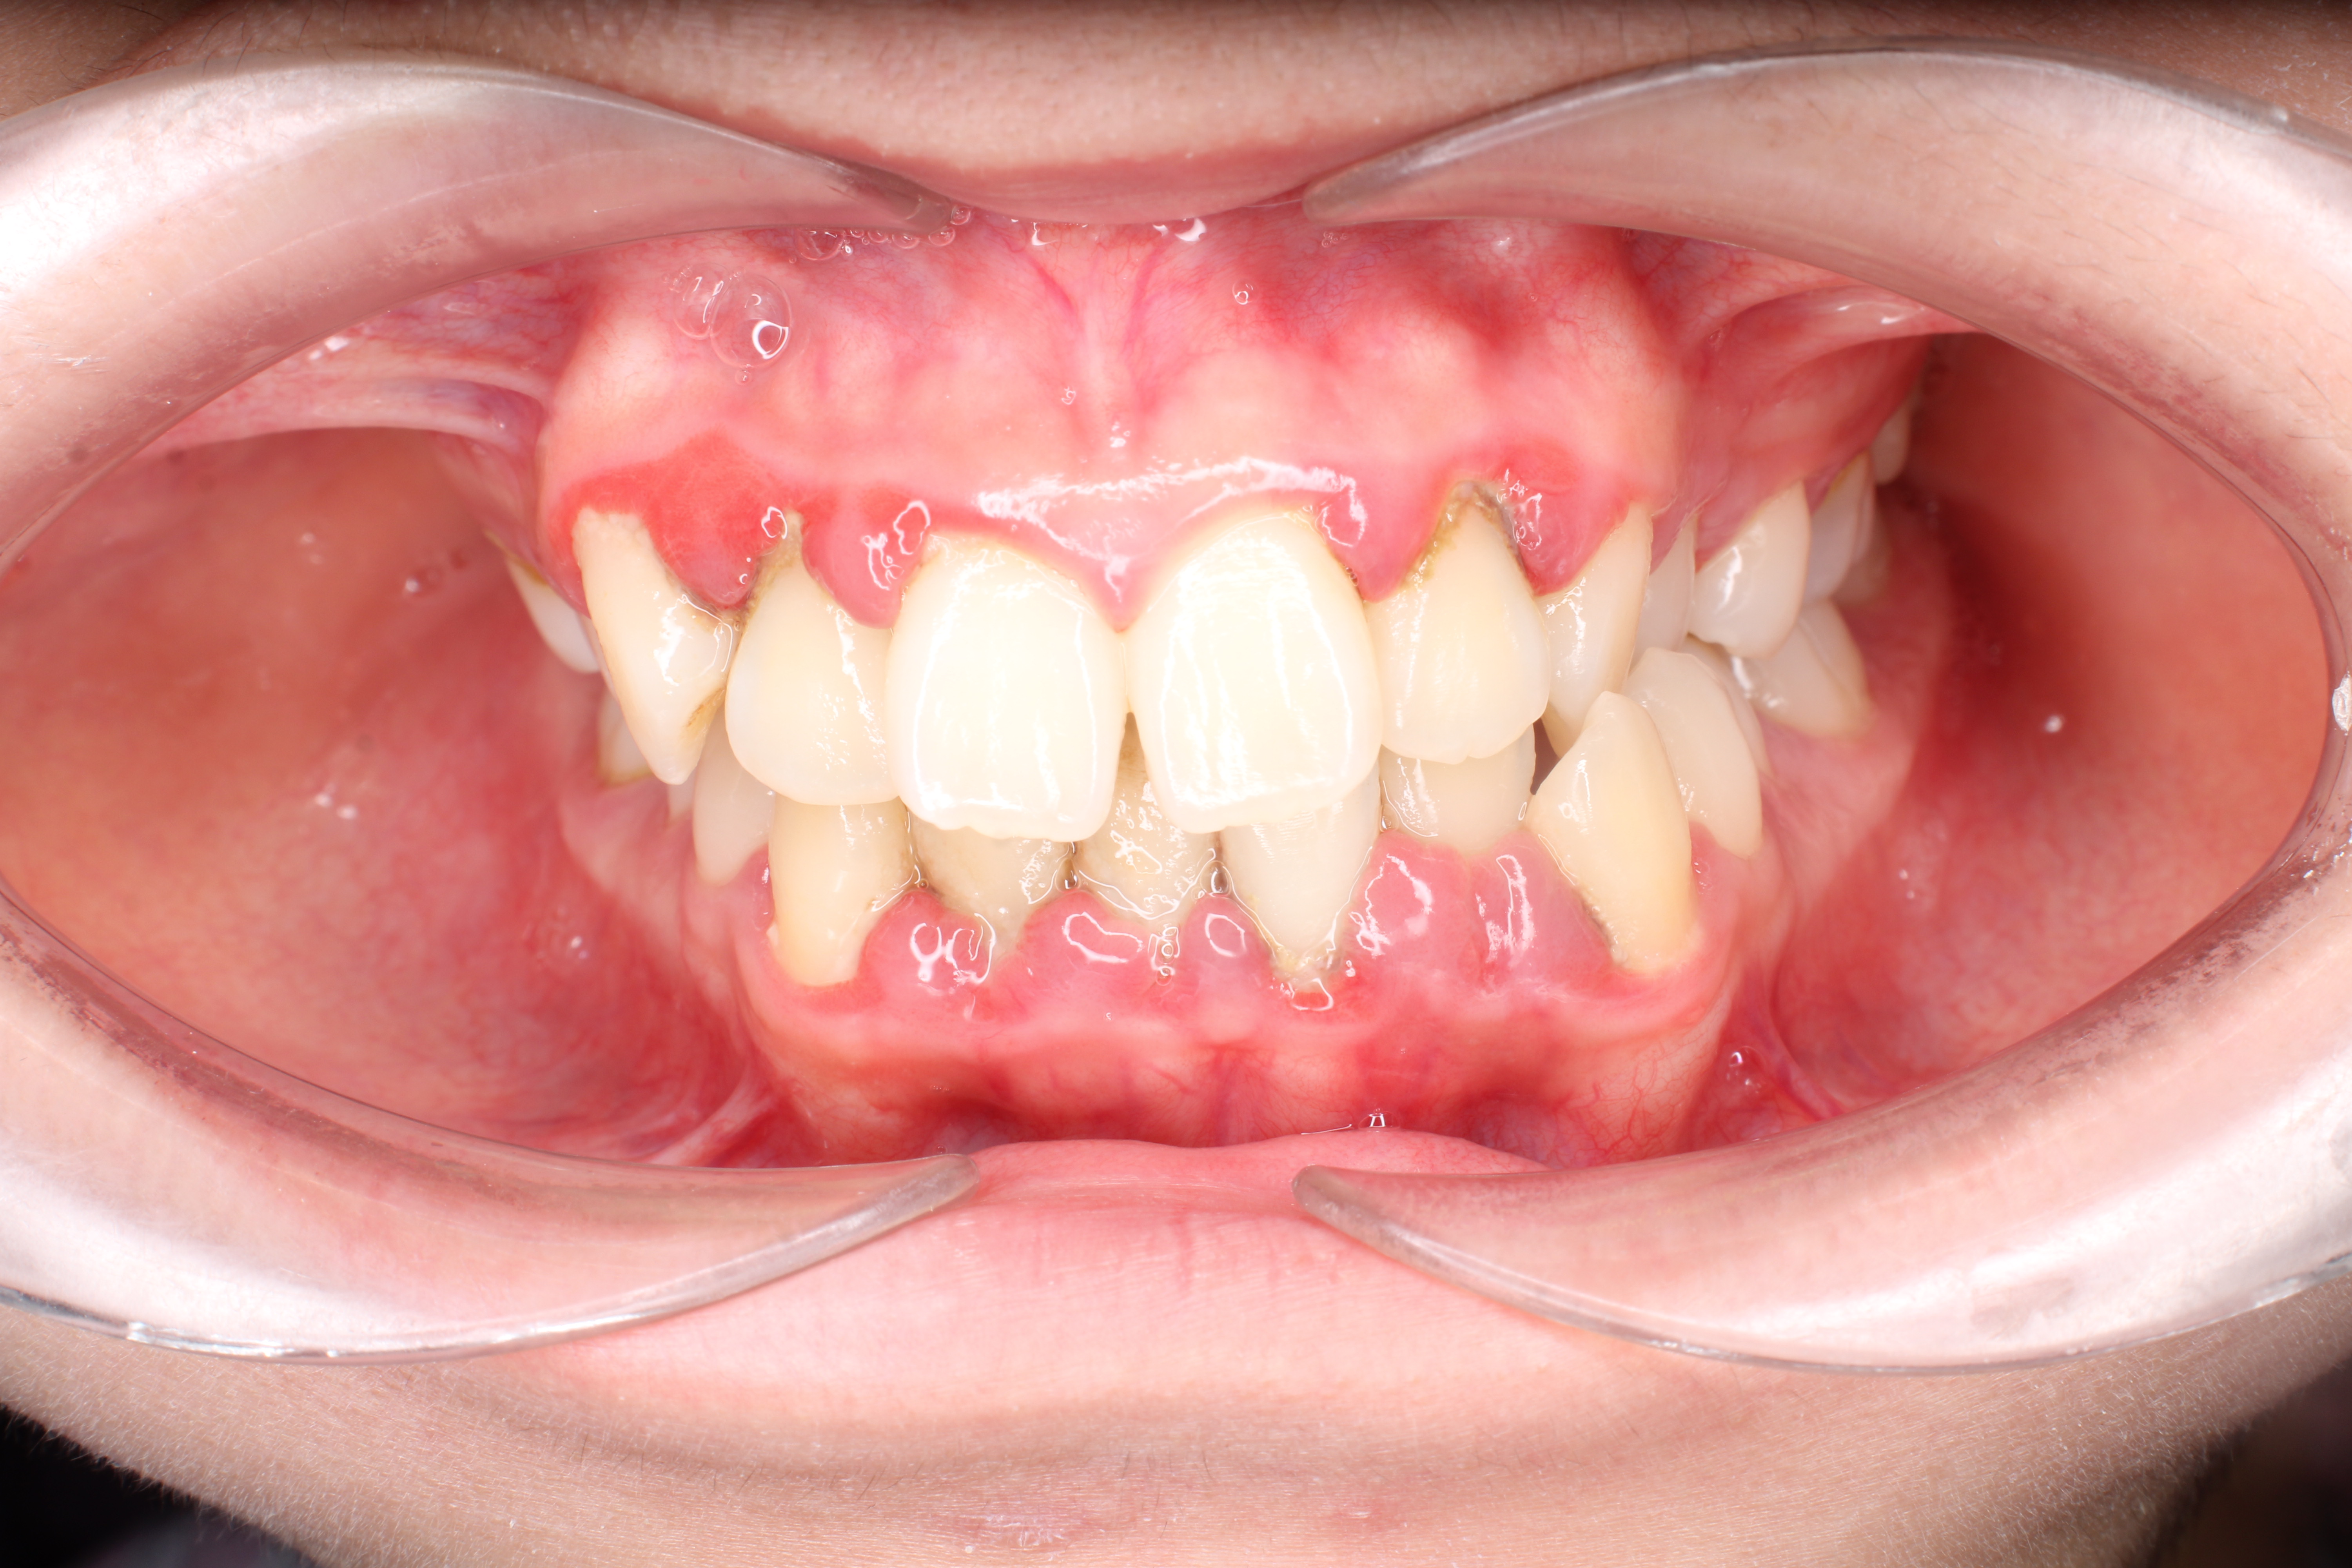

Người mắc bệnh lý về răng miệng chưa được điều trị

Một trong những nhóm điển hình thuộc diện những người không nên niềng răng là người đang gặp các bệnh lý răng miệng như viêm lợi, sâu răng, viêm nha chu hoặc các bệnh lý ở chân răng/chóp răng. Khi răng, nướu hoặc xương ổ răng không khỏe mạnh, lực tác động từ khí cụ chỉnh nha sẽ khiến tình trạng trở nên trầm trọng hơn. Do đó, với những trường hợp này, bác sĩ sẽ yêu cầu điều trị triệt để bệnh lý trước khi bắt đầu niềng răng.

Các bệnh lý viêm nướu, viêm nha chu, tụt lợi, viêm quanh răng cần được điều trị trước khi niềng răng

Tại Nha khoa Lạc Việt Intech, các bệnh lý viêm lợi, sâu răng, ... sẽ được điều trị miễn phí trước khi tiến hành gắn mắc cài niềng răng. Tùy vào tình trạng bệnh lý của từng người, quá trình điều trị này có thể mất vài ngày hoặc vài tuần.